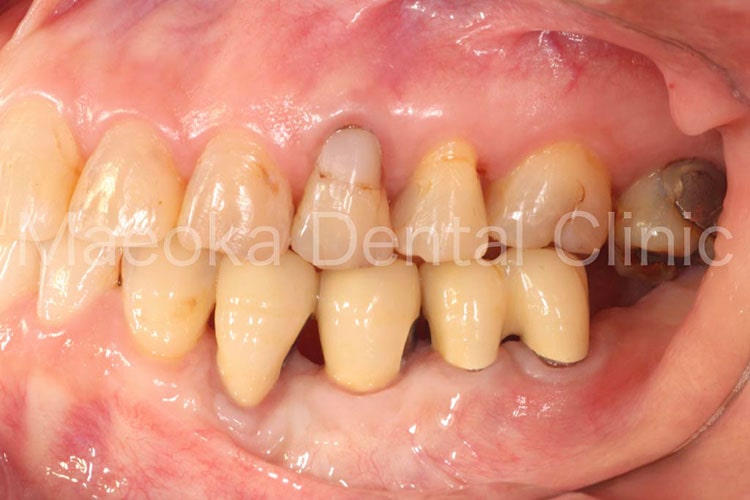

患者さんは49歳女性の方で、「全体的にしっかりと治したい」という主訴で来院されました。

出産を機にお口の環境が悪くなっていったとのことでしたが、勇気が出せずになかなか歯科を受診できなかったそうです。

診査を行うと奥歯の噛み合わせが失われており、審美面、機能面ともに大掛かりな介入が必要な状態でした。

はじめに患者さんから伺った情報を基に、現在の環境になってしまった根本的な原因を模索し、原因除去を行っていきました。その後、歯の移植(右下5を右上3に移植)、部分的な矯正などを行った上で審美的な範囲はセラミックスを用いた被せ物、歯の削除量を最小限にするために見えない箇所は金属を用いた被せ物で最終的な修復を行いました(一部表面的な虫歯は残っていますが、患者さんと相談した上で、今の段階で積極的に削ることは避け、経過観察を行うこととしています)。

プロビジョナルレストレーション(精密な仮歯)を入れた上で機能上問題ないことを確認するなどチェック期間にも時間を要したため、5年に及ぶ治療期間を要しましたが、残りの患者さんの人生の長さを考えると必要十分な治療であったと考えます。

保存不可能と思われる歯が多数ある中ではありましたが、結果として抜歯に至った歯は3本のみで、インプラントを用いることなく、患者さん自身の歯でお口の環境を再構築することができました。

今後はメインテナンスで治療終了時の環境を長期的に維持できるように努めていきます。

治療前(右側方面)

治療後(右側方面)

治療前(左側方面)

治療後(左側方面)